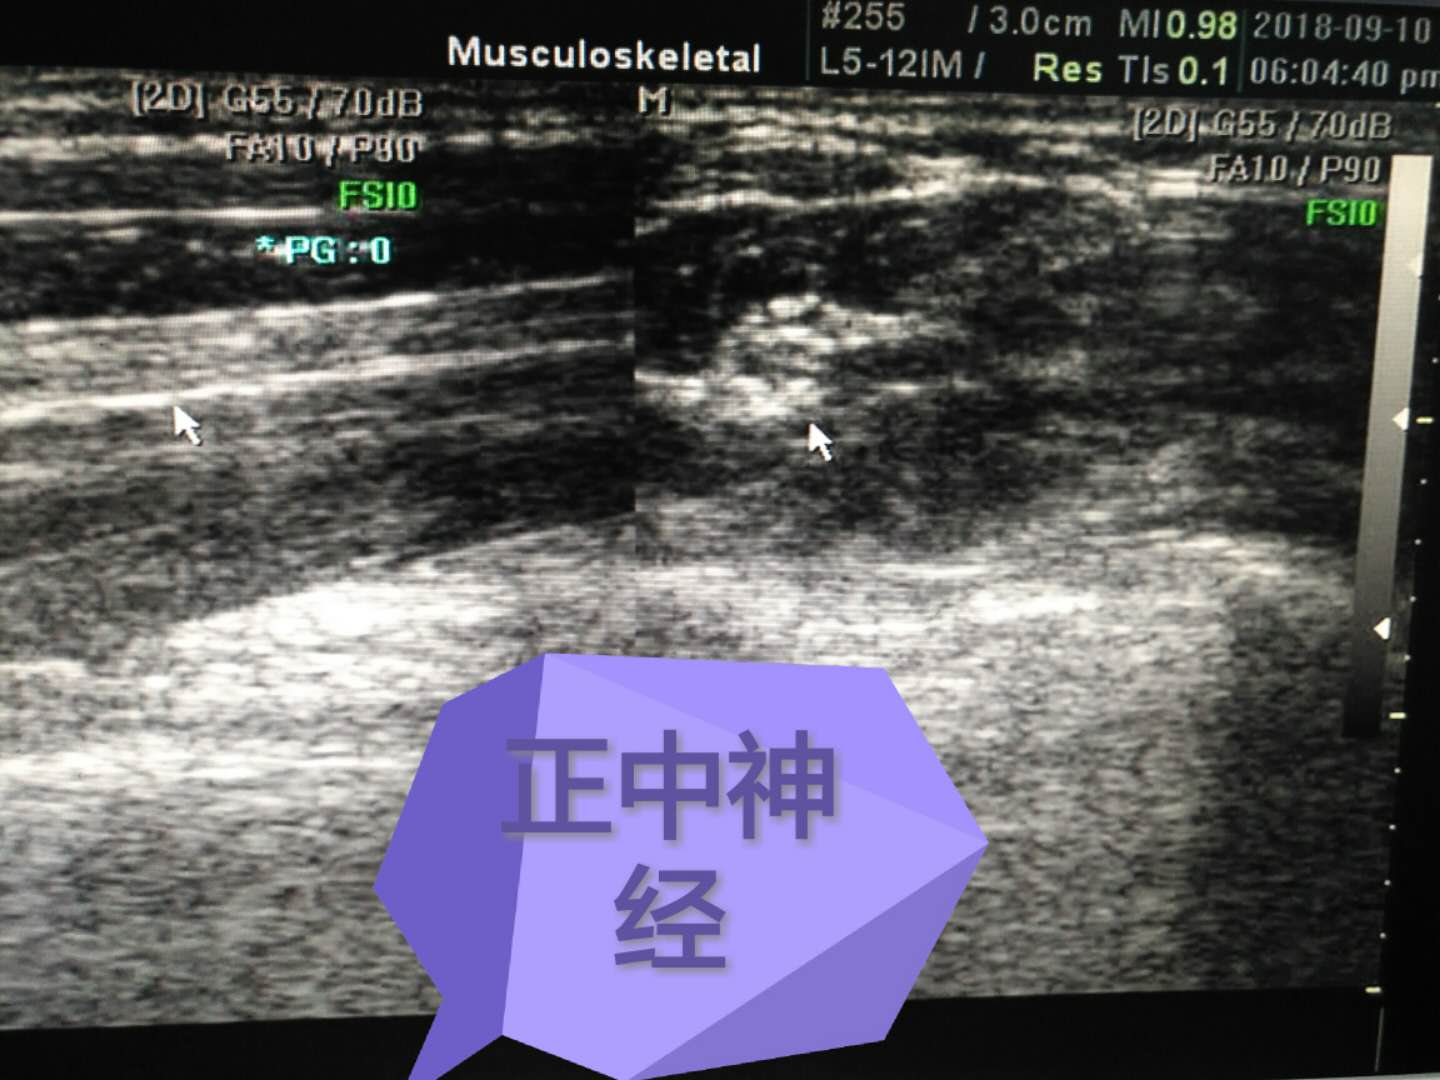

正中神經(jīng)

科室專(zhuān)業(yè)特色:產(chǎn)科四維、腔內超聲、胃超聲、肌肉、肌腱、關(guān)節、外周神經(jīng)超聲等。優(yōu)勢:無(wú)創(chuàng )、無(wú)輻射、實(shí)時(shí)、便捷。